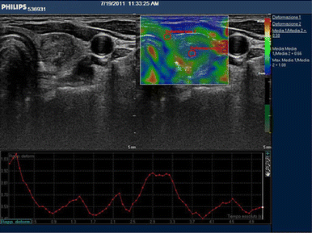

The aim of this study was to determine the accuracy of elastosonography in the differential diagnosis of thyroid nodules using a qualitative [evaluation of the stiffness score (SS)] and quantitative assessment [evaluation of the strain ratio (SR)].

Forty-four nodules were malignant (TIR ≥ 3) and 324 benign on cytological analysis. Considering a cut-off of SS > 2, we had 91 % sensitivity, 68 % specificity, 27 % PPV and 98 % NPV. Considering a cut-off of SR ≥ 3.28, we had 81.8 % sensitivity, 82.7 % specificity, 39.1 % PPV and 97.1 % NPV.

The SR calculation did not provide additional data to the SS, which remains the elastosonography benchmark. It will be necessary to validate these preliminary data by larger prospective randomised trials.